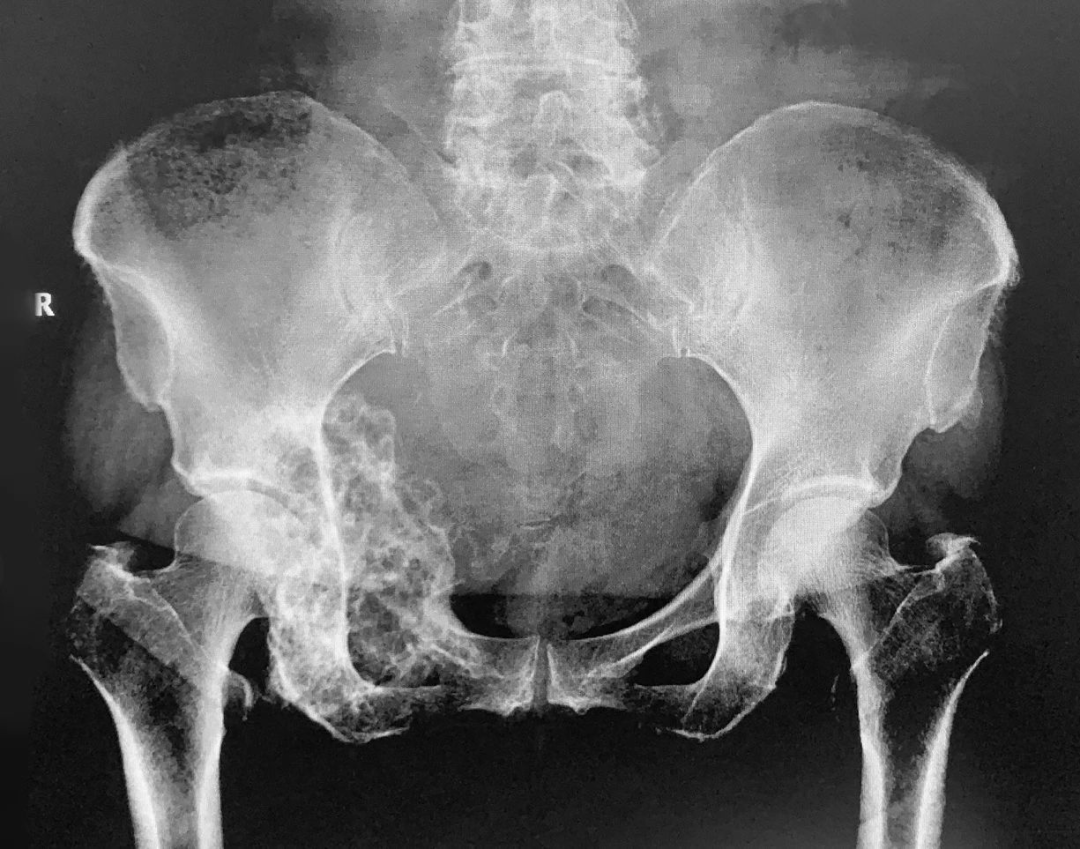

继往开来热情不减再接再厉奋力实践赤峰学院附属医院骨外四病区在骨盆

紫薇帝星助力中科大附属第一医院西区骨科成功实施保肢手术